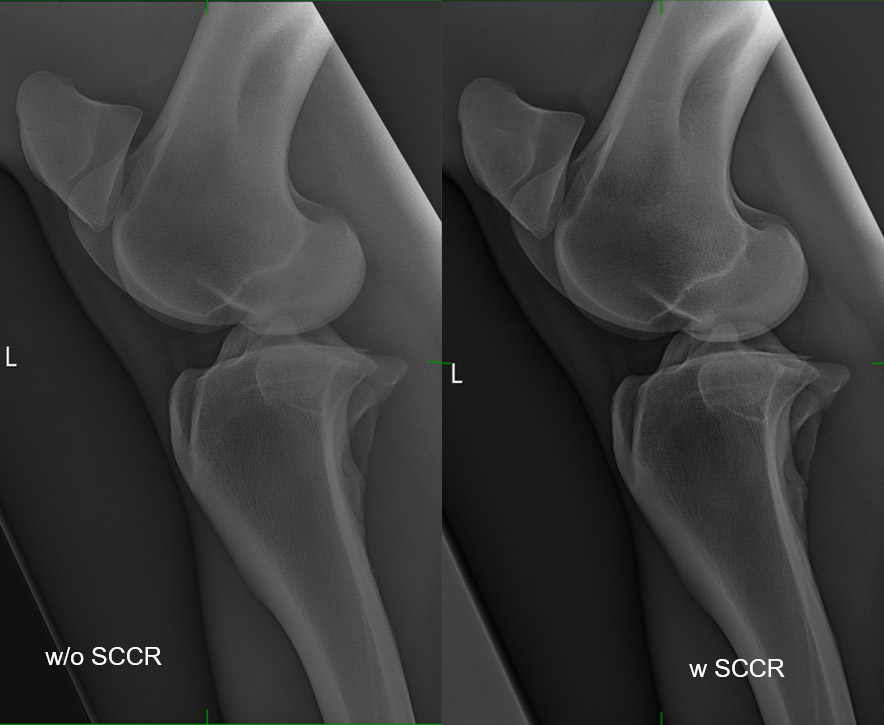

CANON Scatter Correction

Exzellenter Bildkontrast ohne Raster

• Überlegene Bildqualität ohne Verwendung eines physischen Rasters.

• Der Bildkontrast wird durch die Verrechnung von durch Streustrahlen auftretendem Bildrauschen verbessert.